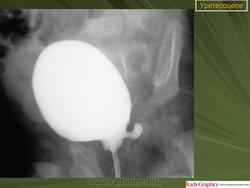

Уретероцеле.

Приложения: